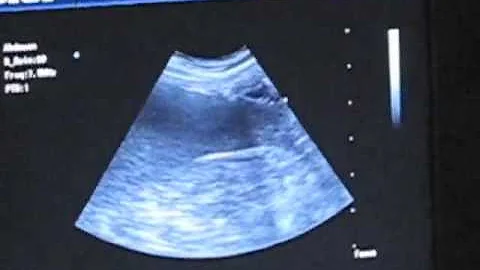

Ultrasound Of The Canine Spleen

Book a 1-on-1 Clarius demo: https://clarius.com/getdemo In this video Dr. Edwards shows patient and scanner positions for a ...